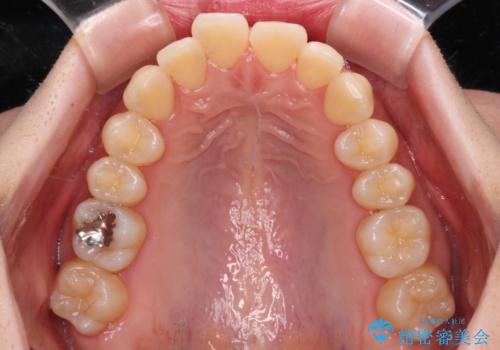

- 口元の閉じにくさを気にして来院された患者様です。

上下ともに歯列が前方に突出していたため、上下左右の第一小臼歯4本を抜去し、ワイヤー装置による矯正治療を行うこととしました。

舌の突出癖による影響もあったため、舌のトレーニングを並行して実施しました。